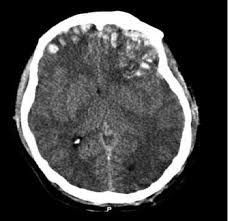

Cerebral contusions are scattered areas of bleeding on the surface of the brain, most commonly along the undersurface and poles of the frontal and temporal lobes. They occur when the brain strikes a ridge on the skull or a fold in the dura mater, the brain’s tough outer covering. These bruises may occur without other types of bleeding or they may occur with acute subdural or epidural hematomas.